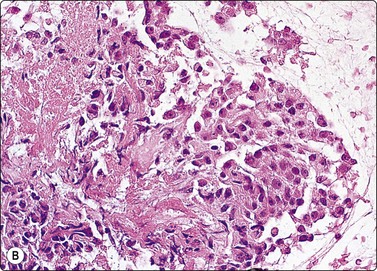

Malignant thymoma (Figs 9.2, 9.7 and 9.8)1-3,18,25,64,70-74

Thymic carcinomas are very uncommon cytologically malignant tumors with a wide variety of morphological appearances including keratinizing and nonkeratinizing squamous, sarcomatoid, anaplastic large cell, basaloid, mucoepidermoid, clear cell and small cell types.1-3 A cytological diagnosis of carcinoma may be made by FNB. Smears are variably cellular and usually dominated by loosely cohesive large malignant cells diagnostic of carcinoma. Most are composed of large tumor cells with solitary clearly malignant nuclei, with or without prominent nucleoli. As expected, their smear appearance resembles the underlying histopathology. Reports of FNB diagnosis of rare subtypes such as basaloid and mucoepidermoid carcinomas area also reported.73,74

image image image

Fig. 9.7 Thymic carcinoma

(A) Disorganized aggregate of pleomorphic malignant cells with macronucleoli; (B) Cell block showing poorly differentiated large cell carcinoma; (C) Staining of tumor cells for CD5 (A, Pap, HP; B, Cell block. H&E, HP; C, cell block, IPOX).